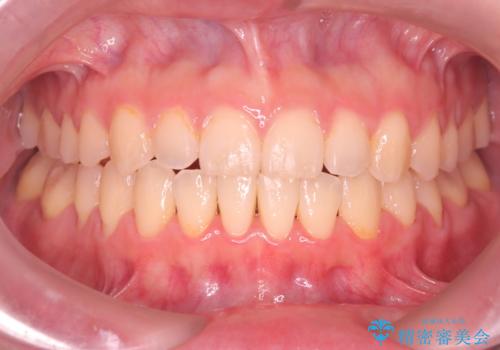

- 患者様は、**前歯の叢生(がたつき)**を気にされて来院されました。

できるだけ歯を削らずに、自然な歯並びを手に入れたいというご希望がありました。

診査の結果、中等度の叢生であったため、インビザラインモデレートでの対応が可能と判断しました。

歯へのダメージを抑えるため、IPR(歯間削合)は必要最小限にとどめる方針としました。